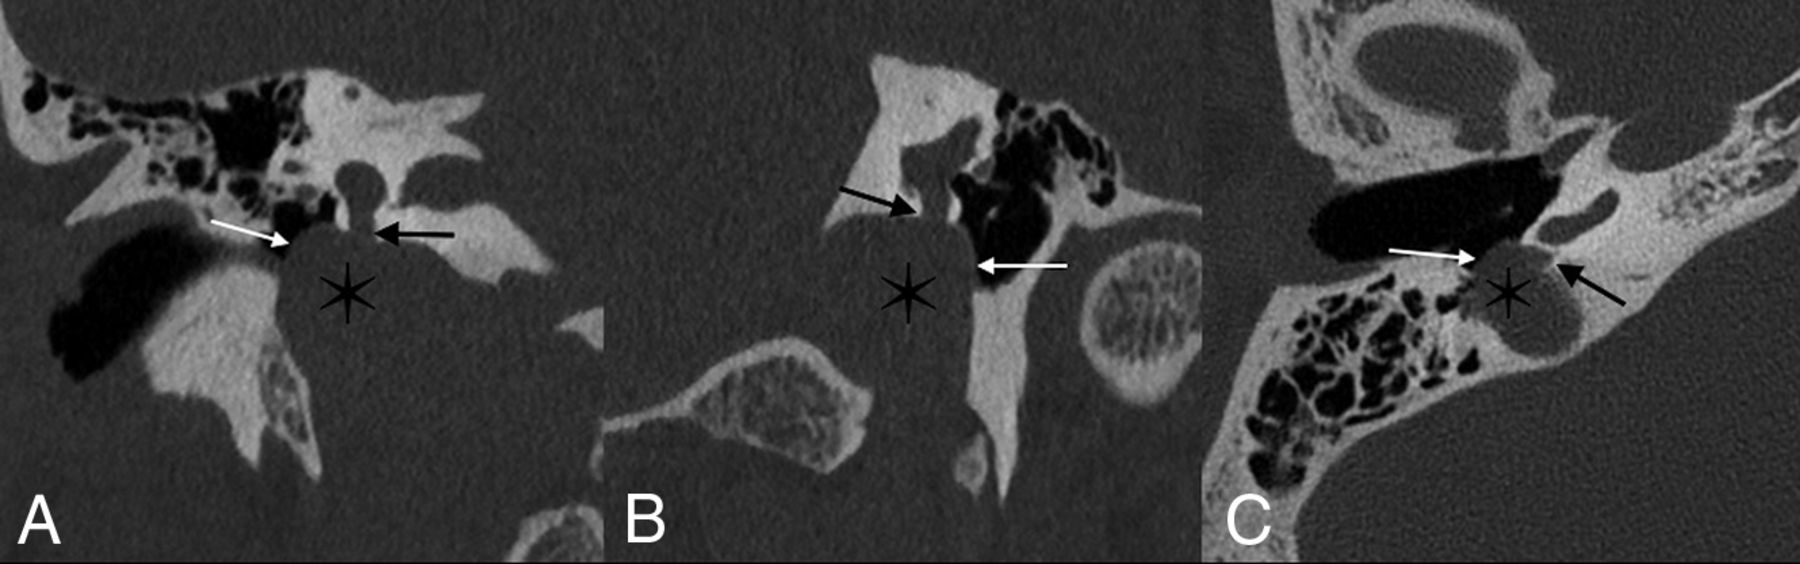

High-riding jugular bulbs, dehiscent bulbs, and jugular diverticula are often asymptomatic.41 However, they may also present with pulsatile tinnitus or, less commonly, conductive hearing loss, likely related to encroachment by the bulb on the round window, ossicular chain, or tympanic membrane (Fig 9).41,42 The incidence in which the round window membrane is specifically involved is rare; 1 histologic analysis of temporal bones identified 2 such cases in 1579 specimens (0.1%).43

Jugular bulb anomalies. Coronal (A), Pöschl (B), and axial (C) images demonstrate a high-riding jugular bulb (asterisk) that extends into the round window niche (straight black arrows). The bony margins overlying the jugular bulb within the middle window are markedly thinned, compatible with dehiscence (white arrows).

Imaging findings vary on the basis of the type of jugular bulb abnormality. High-riding bulbs typically occur as an isolated finding, in which the dome of the jugular bulb is within 2 mm of the internal auditory canal (IAC) floor (though definitions vary).44,45 A high-riding bulb may extend further superolaterally, erode the sigmoid plate, and protrude into the middle ear cavity; this dehiscence is best seen on CT as thinning and/or absence of bone between the bulb and middle ear structures.44 Finally, diverticula will appear as distinct outpouchings from the bulb. Any jugular bulb anomaly seen on CT should be closely examined for the presence of abutment of the bulb on the round window membrane, niche, or other middle ear structures.